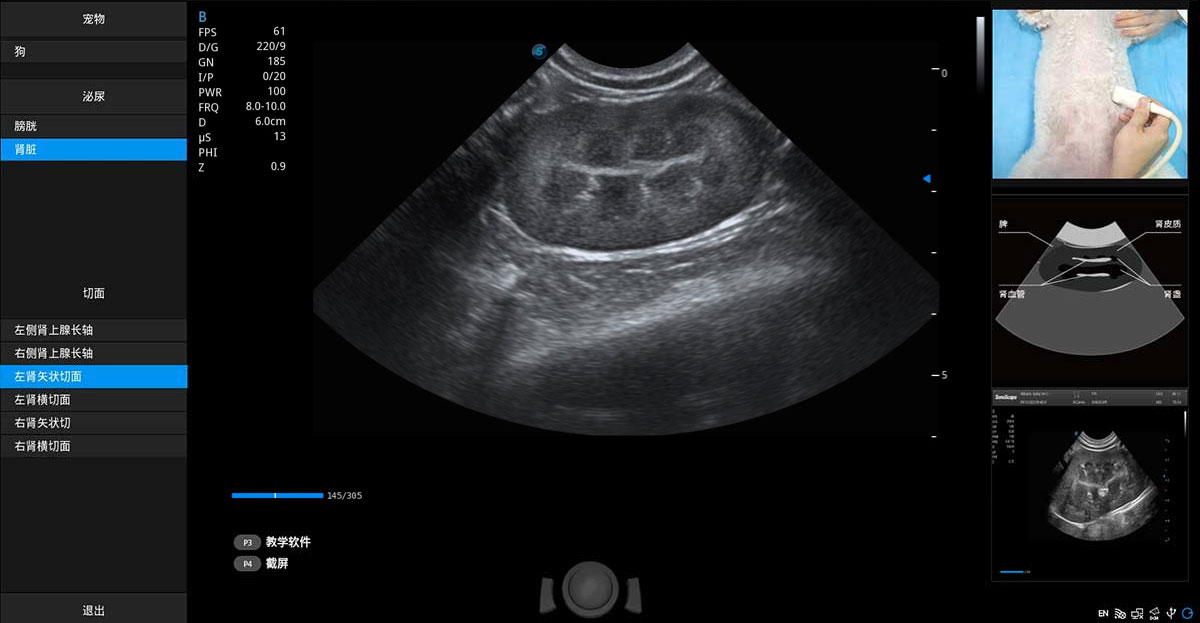

提供解剖示意图、标准超声图像、扫查手法涂和操作者实时检查图像,指导操作者进行标准切面的正确扫查。